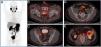

Radiotherapy is a treatment with curative intent, both in patients with primary diagnosis of prostate cancer (PCa) and in patients presenting with biochemical recurrence after radical prostatectomy (RP). Moreover, the use of stereotactic body radiotherapy as a metastasis directed therapy in patients with oligometastatic PCa has significantly increased in the recent years. Conventional imaging techniques, including transrectal ultrasound, computed tomography (CT), morphologic magnetic resonance and bone scintigraphy have traditionally played a minor role in all those clinical scenarios due to its low diagnostic accuracy. The recent development of the positron emission tomography (PET) radiotracer 68Ga-PSMA binding to the prostate specific membrane antigen (PSMA), a transmembrane glycoprotein overexpressed in PCa cells, has shown promising results. Detection rates for PCa lesions are higher than CT and higher than the best technique available, the PET/CT with choline. Its superiority has been demonstrated even at very low PSA levels (<1 ng/ml). This increase in diagnostic accuracy represents a potential impact on patient management, especially in radiotherapy. Even if this imaging technique is already available for routine clinical practice in some European countries, in Spain, unfortunately, there is very limited access. In this review, we analyze the main studies that investigate the usefulness of 68Ga-PSMA PET/CT in patients with PCa and its potential impact on radiotherapy treatments. In addition, we compared the 68Ga-PSMA PET/CT, with the multiparametric magnetic resonance imaging and the PET/CT with choline, in the different clinical scenarios.